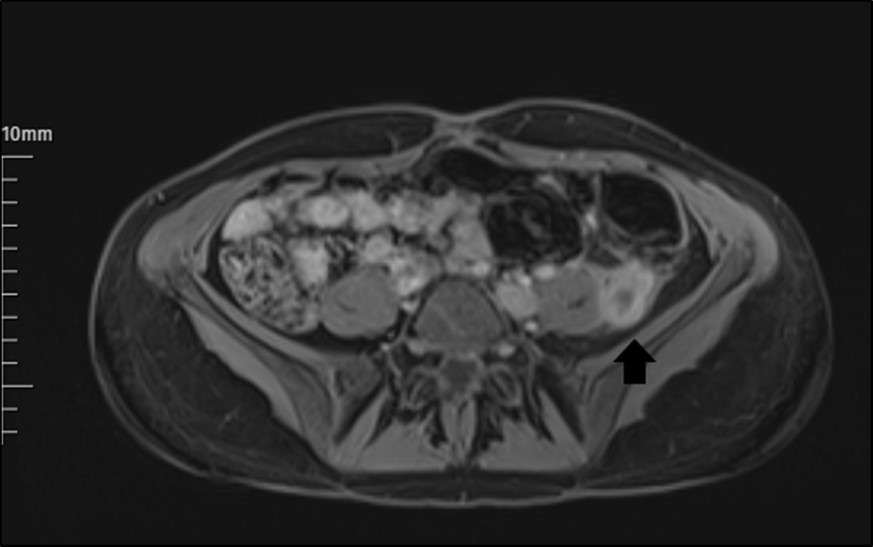

The abdomen and pelvis area were examined by MRI with contrast. It revealed a markedly dilated LOV containing abnormal soft tissue attenuation material throughout, indicating ovarian vein thrombosis. The aspect of a LOV in MRI images was persistent, with signs of increased signal in this area (Figure 1). Subsequent inferior abdominal MRI demonstrated a thrombus starting from the LOV to the level of the left renal vein. There is an enhancement in the vein walls (thrombophlebitis).

Figure 1.The appearance of a left ovarian vein in MRI.